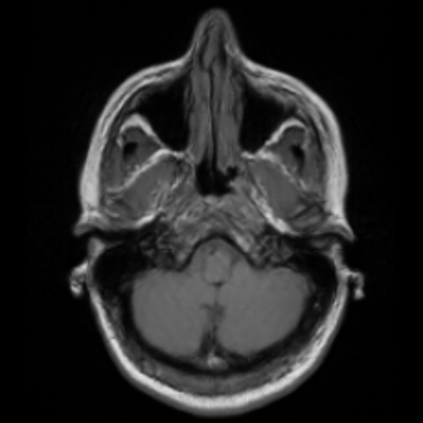

Motion artifacts are a primary source of magnetic resonance (MR) image quality deterioration with strong repercussions on diagnostic performance. Currently, MR motion correction is carried out either prospectively, with the help of motion tracking systems, or retrospectively by mainly utilizing computationally expensive iterative algorithms. In this paper, we utilize a novel adversarial framework, titled MedGAN, for the joint retrospective correction of rigid and non-rigid motion artifacts in different body regions and without the need for a reference image. MedGAN utilizes a unique combination of non-adversarial losses and a novel generator architecture to capture the textures and fine-detailed structures of the desired artifacts-free MR images. Quantitative and qualitative comparisons with other adversarial techniques have illustrated the proposed model's superior performance.